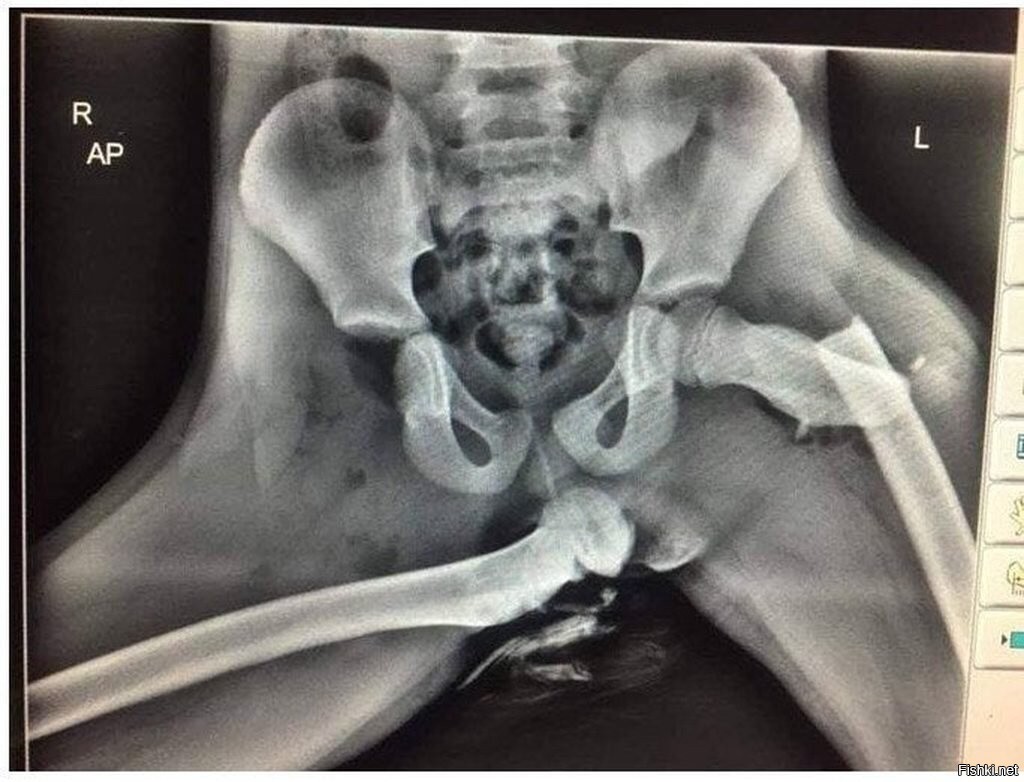

Надо не так. Надо показать то видео, где вот так же девица сидела, а машина попала в дтп не знаю выжила ли она после операций, но при первом обследовании у неё был раздроблен таз, бедренные кости вошли в брюшную полость и в грудную клетку и собственно тоже были множественные преломы всех костей. Короче ужас кошмарный

Была история, что девушка в Америке ехала тоже поставив ноги на панель. Машина попала в аварию и ее ноги оторвались от тазобедренных суставов. Короче инвалидность в коляске на всю жизнь.

А представьте большую скорость и дтп + пристегнутый пассажир и сработавшие подушки. Видел рентгеновские снимки, не завидую вообще